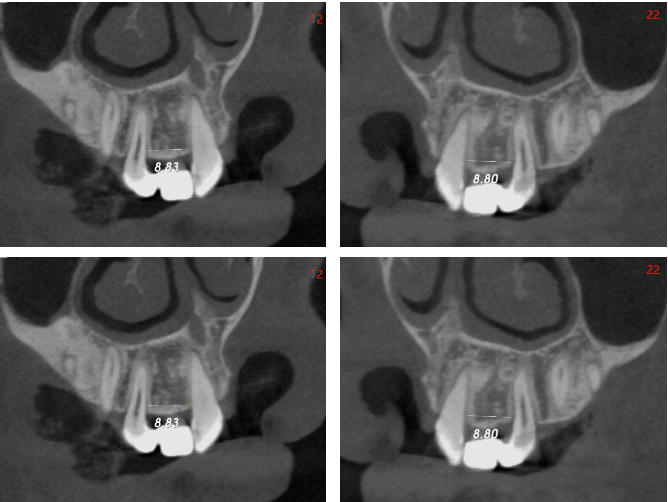

影像学检查

骨宽度稍欠,骨宽度约4.0mm,骨高度约15mm

邻牙未见明显异常

术前术后对比,22根方偏唇侧:

12牙

22牙

偏斜可能原因:腭侧皮质骨阻力较大,使钻针往唇侧偏斜